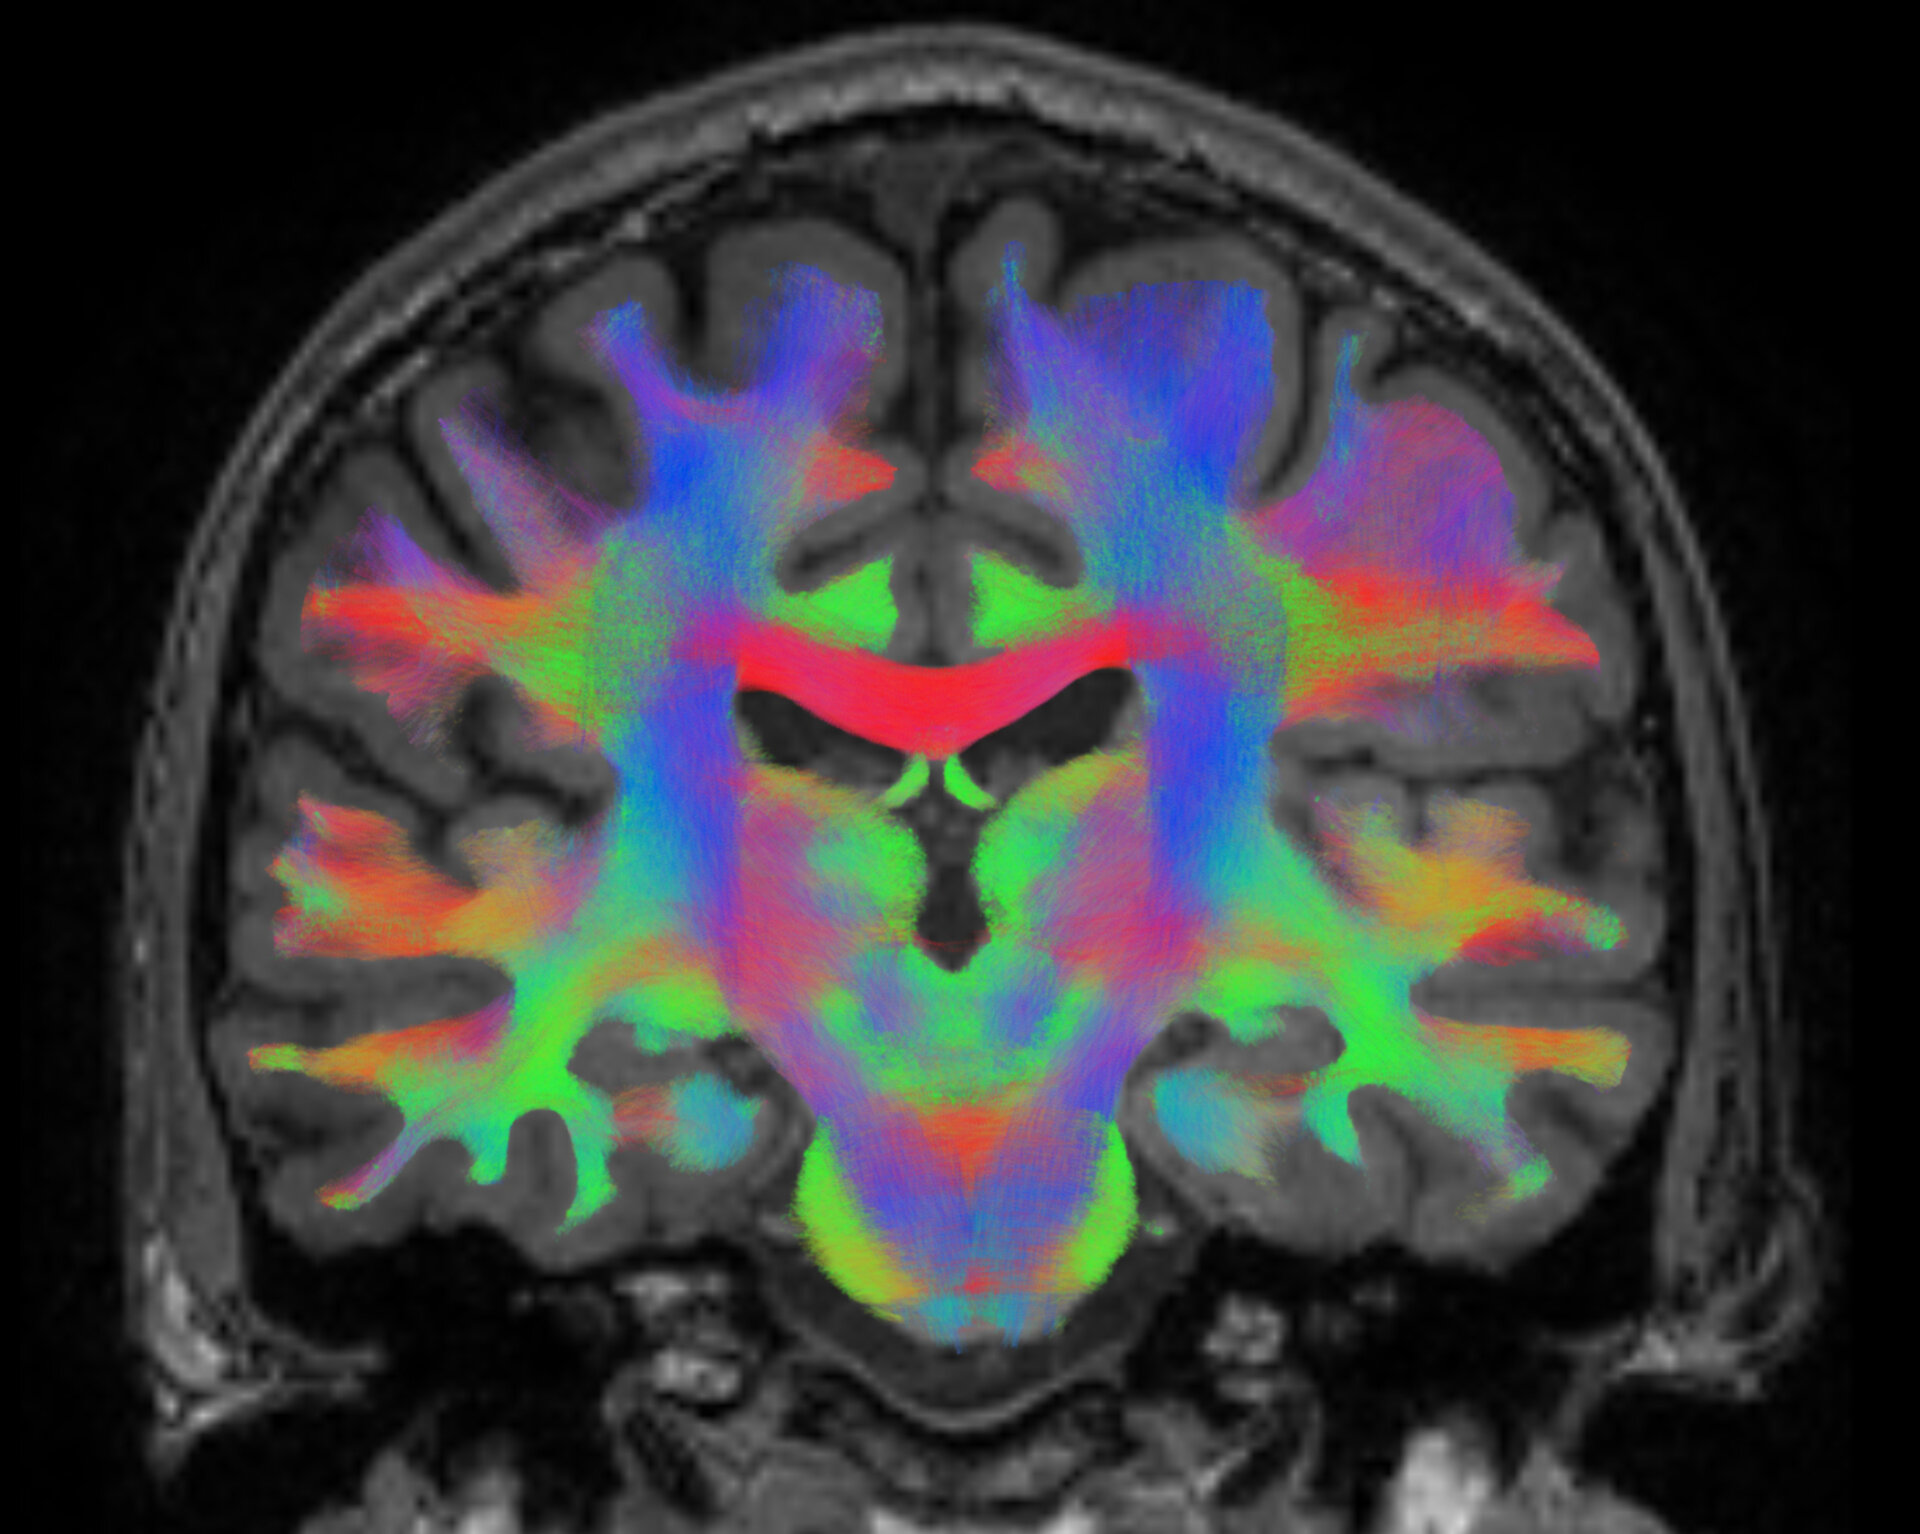

ESA’s BRAIN DTI experiment, assessing how the brain adapts to spaceflight making use of MRI brain scans, has been honoured with the Compelling Results Award in Human Health in Space at the International Space Station Research and Development Conference (ISSRD), held at the end of July in Seattle, USA. The science team is led by Prof. dr. Floris Wuyts from the University of Antwerp in Belgium and consists of a consortium of several European and international investigators.

The experiment is currently running on ISS crew and also has (planned) activities on several ESA ground-based analogues. In particular, it assesses functional and structural changes to the brain after spaceflight. Alterations to the different brain tissues have been found, some still visible also 6 months after returning from space. Further research is needed to delineate the clinical significance of these brain changes on crew health and performance.